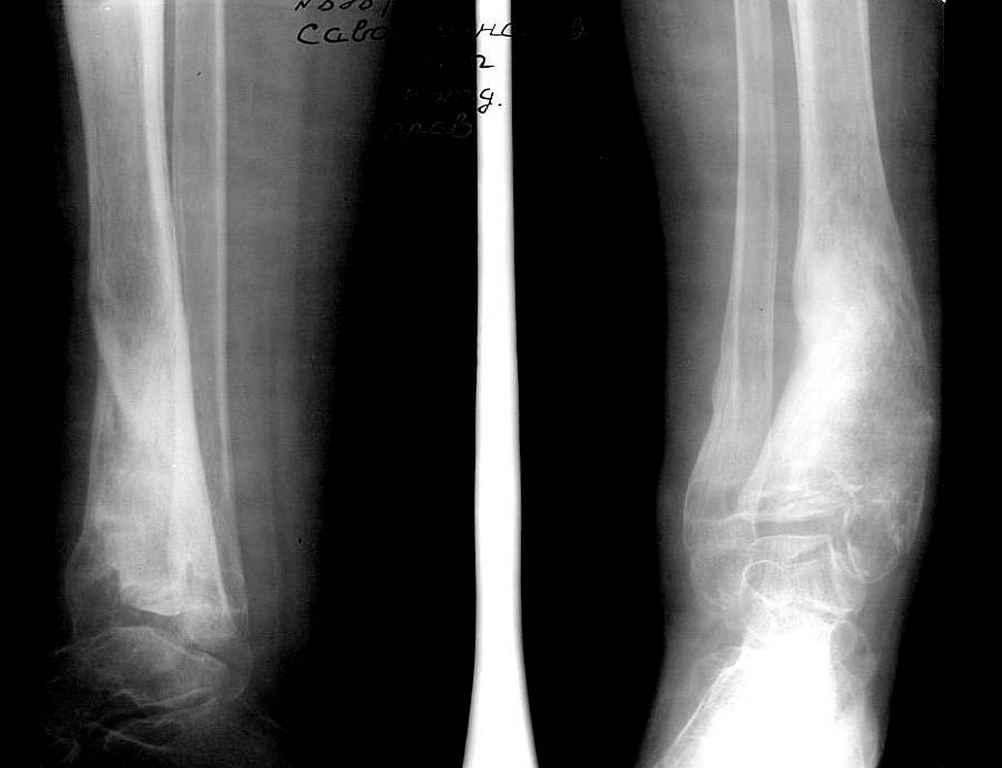

Девушка 17 лет: боли в голеностопном суставе,ограничение движений в суставе,укорочение голени,хромота Из анамнеза в раннем детском возрасте перенесла гематогенный остеомиелит дистального отдела большеберцовой кости - зона роста частично закрылась сформировалась варусная деформация голеностопного сустава + укорочение костей голени на 6 см Произведена корригирующе-удлиняющая остеотомия сначала большеберцовой,затем малоберцовой костей, устранена деформация, ликвидировано укорочение. С возрастом наросло укорочение до 3 см,клинически умеренная вальгусная деформация голеностопного сустава. Объём движений в суставе в пределах 15 град. Отмечает переодически болевой синдром, после осевой перегрузки,пользуется обувью с компенсацией, ортезом на голеностопный суставВопрос: есть ли показания для оперативного лечения: артропластика? артродез? голеностопного сустава. Какие мысли,коллеги?